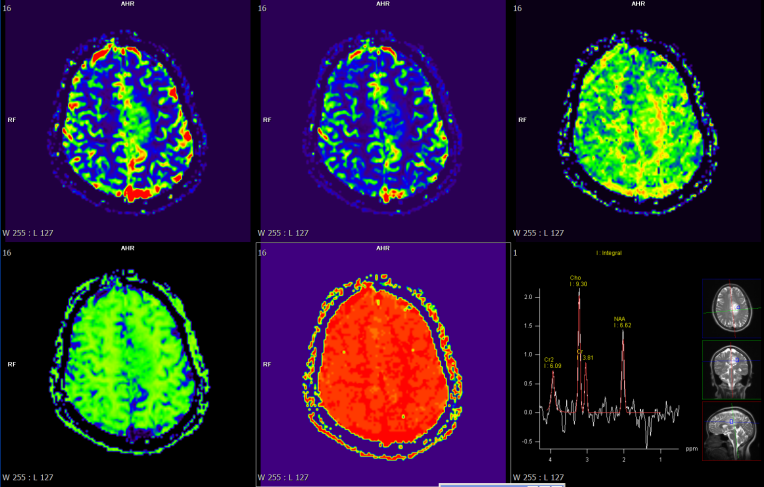

磁共振檢查方面,開展了高技術(shù)的增強(qiáng)掃描動態(tài)分析,動態(tài)灌注掃描、波譜分析,為腫瘤鑒別提供了有效方法,比如腦內(nèi)膠質(zhì)瘤、淋巴瘤的鑒別。

富血供病變---高級別膠質(zhì)瘤